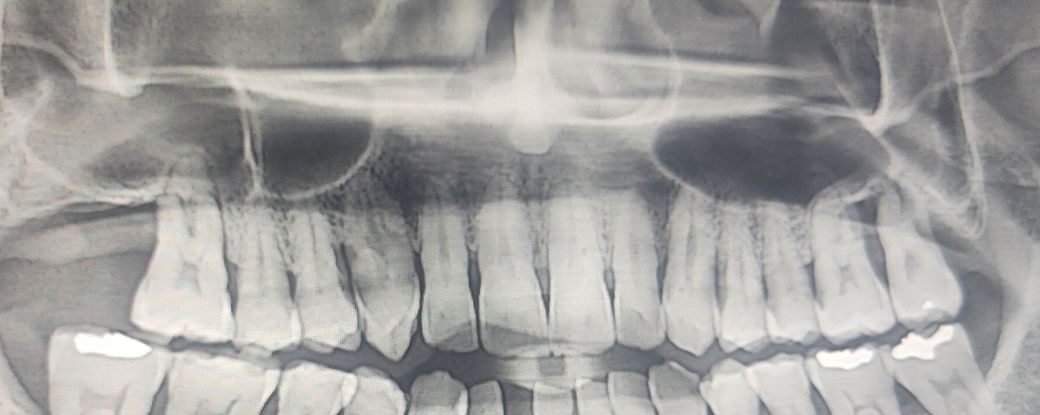

치과 1에서는 (사진기준) 우측 상단 치아 1개만 발치가 필요하고 임플란트없이 쓰다가 나중에 임플란트 하라는 의견을 받았습니다. 어금니는 모두 흔들리지는 않아서 기능상 문제는 없지만 우측상단 치아 잇몸뼈가 너무 녹아서 옆치아에 영향을 주기때문에 발치는 할 필요가 있다는 의견입니다.

치과3은 1) 사진 기준으로 우측 상단에 치아2개 발치후 임플란트 2개, 2) 좌측 상단 치아 1개 발치후 임플란트 2개, 총 4개 어금니 임플란트가 급하다는 의견입니다.

그 이유는 뿌리뼈가 너무 녹아서 이대로 시간이 흐르면 상악동까지 문제가 생길 수 있고, 그러면 아예 임플란트 불가능 하다는겁니다. 상악동에 구멍이 뚫릴수도 있다고 말씀하시는데, 걱정이 엄청 됩니다. 당장 안하면 큰일날 것처럼 말씀하십니다.

자연치아가 당연히 임플란트보다는 좋으나 현재 잇몸뼈가 거의 녹아 위쪽 어금니들은 자연치아라도 제대로 기능하지 못할것 같고 그렇게 오래쓰진 못할 것 같습니다 지금 정리할건 정리하고 임플란트를 하는것도 방법이고 아니면 쓸때까지 쓰고 흔들리거나 불편할때 빼고 임플란트를 하는 방법도 있습니다 한쪽씩 어금니 2개는 같이 묶어서 한꺼번에 하는 것이 좋을 것 같습니다 그래야 씹는힘이 조금이라도 분산됩니다 다만 쓸때까지 쓴다 친다면 잇몸뼈가 그 사이에 더 녹을 수도 있고 임플란트 심는 난이도가 올라갈 수도 있습니다